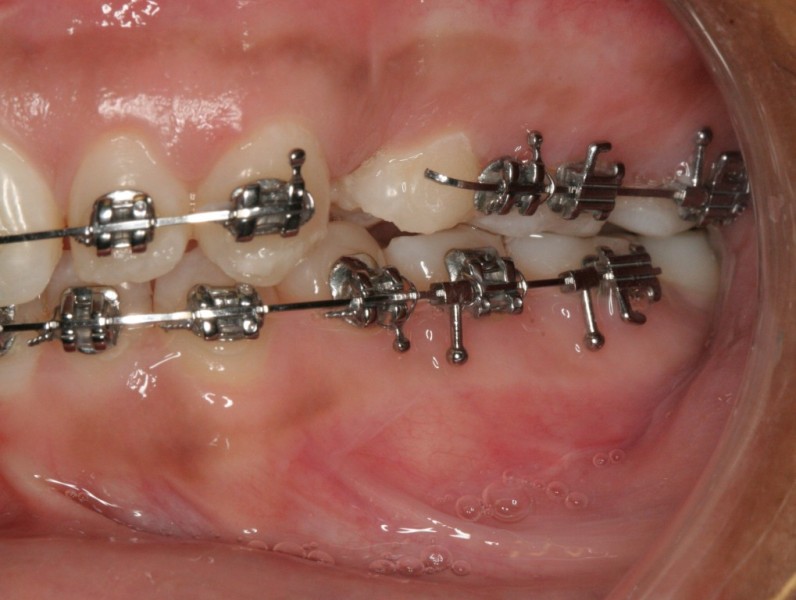

Pretreatment - Patient on Presentation

After Orthodontic Setup - Presurgical